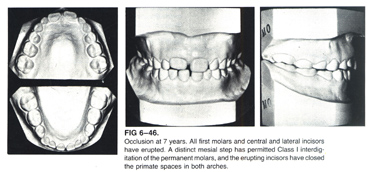

3. An Example of Dentitional Change in Normal Case (by Univ of Michigan)